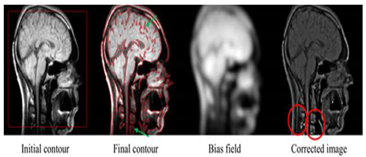

- Level set: consists of representing the segmentation of the contour by the zero level set of a smoothing [108,117,118,119,120,121]. There are two types of methods: geometric and geodesic. Its strong points are the ease of following forms that change topology. Best results for weak and variable signal-to-noise ratios and for non-uniform intensities. Allow to manage any cavity, concavity, convolution, split or fusion. Allow numerical calculations involving curves and surfaces to be performed on a fixed Cartesian grid without having to configure objects. However, the boundaries of the object are not clearly defined by strong image gradients or significant changes in the intensity distribution, this is common in several medical applications, for which image data often suffer from low contrast or fabric noise. In addition, for large images, the execution speed could be very slow and requires manual adjustment of the parameters to obtain optimal results. Possibility of being trapped by an undesirable local minimum which requires additional regularization to obtain the desired minimum.